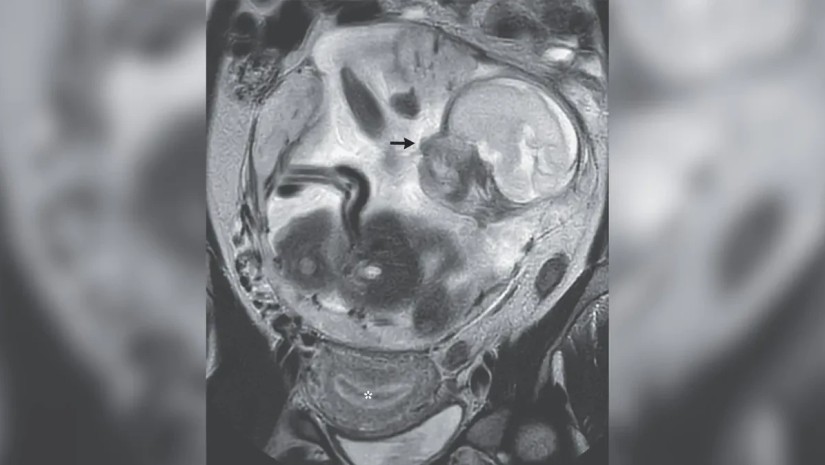

საშვილოსნოში ჩანასახი არ დაფიქსირდა, სამაგიეროდ აღმოჩნდა, რომ ის მუცლის ღრუში უკვე 23 კვირის განმავლობაში ვითარდებოდა. დამატებითმა მაგნიტურ რეზონანსულმა გამოსახულებებმა აჩვენა, რომ ნაყოფი ნორმალურად იყო ფორმირებული და პლაცენტას უკავშირდებოდა, რომელიც ემბრიონის საჭირო ნივთიერებებით მომარაგებას უზრუნველყოფს. თავად პლაცენტა ქალის ხერხემლის დაბოლოებასთან ახლოს, საშვილოსნოს კედელზე იყო მიმაგრებული.